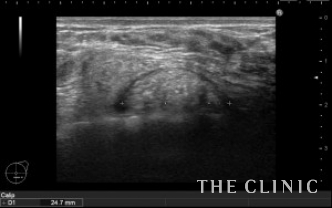

この方は、大胸筋下に充実性のしこりを認めます。

大胸筋下のしこりは、バストの深い層にあるため触れにくいですが、バストのボリュームが小さい方は気になる場合があります。